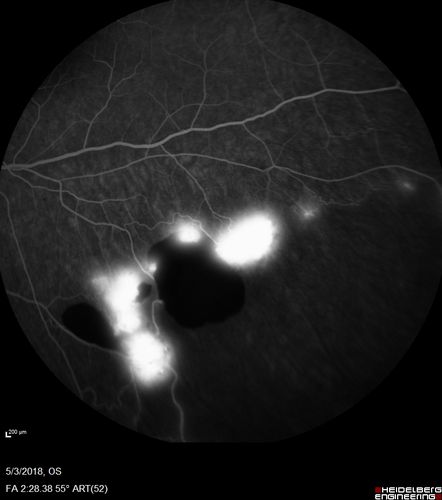

Coats' Disease -51 year old asymptomatic male

20/20 vision - had laser to non-perfusion because of proliferation.